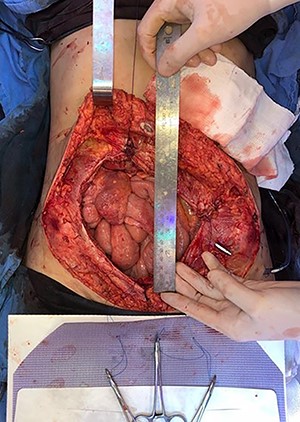

In April 2020, the surgery was performed, with pan-hysterectomy, excision of the AW and skin, pelvic peritonectomy, cecectomy (due to local involvement), partial cystectomy, Hartmann rectosigmoidectomy (Figs 4 and 5), followed by AW partial closure and an intraperitoneal onlay mesh (Open IPOM) in a bridged position with Bard Mesh/BD Sepramesh. Abdominoplasty was performed to allow skin coverage (Figs 6–10). The patient stayed in hospital for 18 days and presented urinary retention. Definitive anatomopathological was HGSC, infiltrating uterus, AW, cecum, rectosigmoid and obturator lymph node metastasis. After cytoreduction, she underwent chemotherapy (carboplatin plus docetaxel).

Surgical specimen of pan-hysterectomy with excision of the abdominal wall and cecectomy.

Pelvis after tumor excision, peritonectomy and lymphadenectomy.